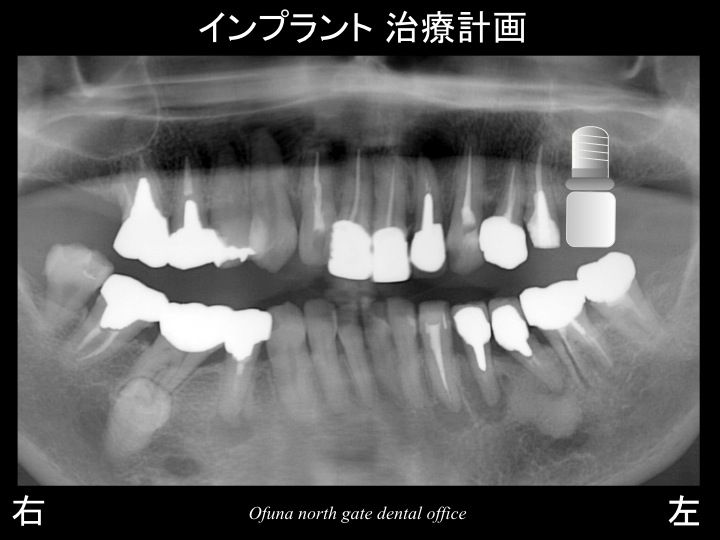

以下が初診時のレントゲンです。

スライド01

スライド02

上顎の左右の奥歯が欠損している状態です。

スライド07

下顎左側の奥歯はそのままにして

患者様のご希望のあった 上顎左側の奥歯に 1本のインプラントを埋入する

治療計画となりました。

スライド09

スライド08

以下が治療終了後のレントゲンです。

スライド10